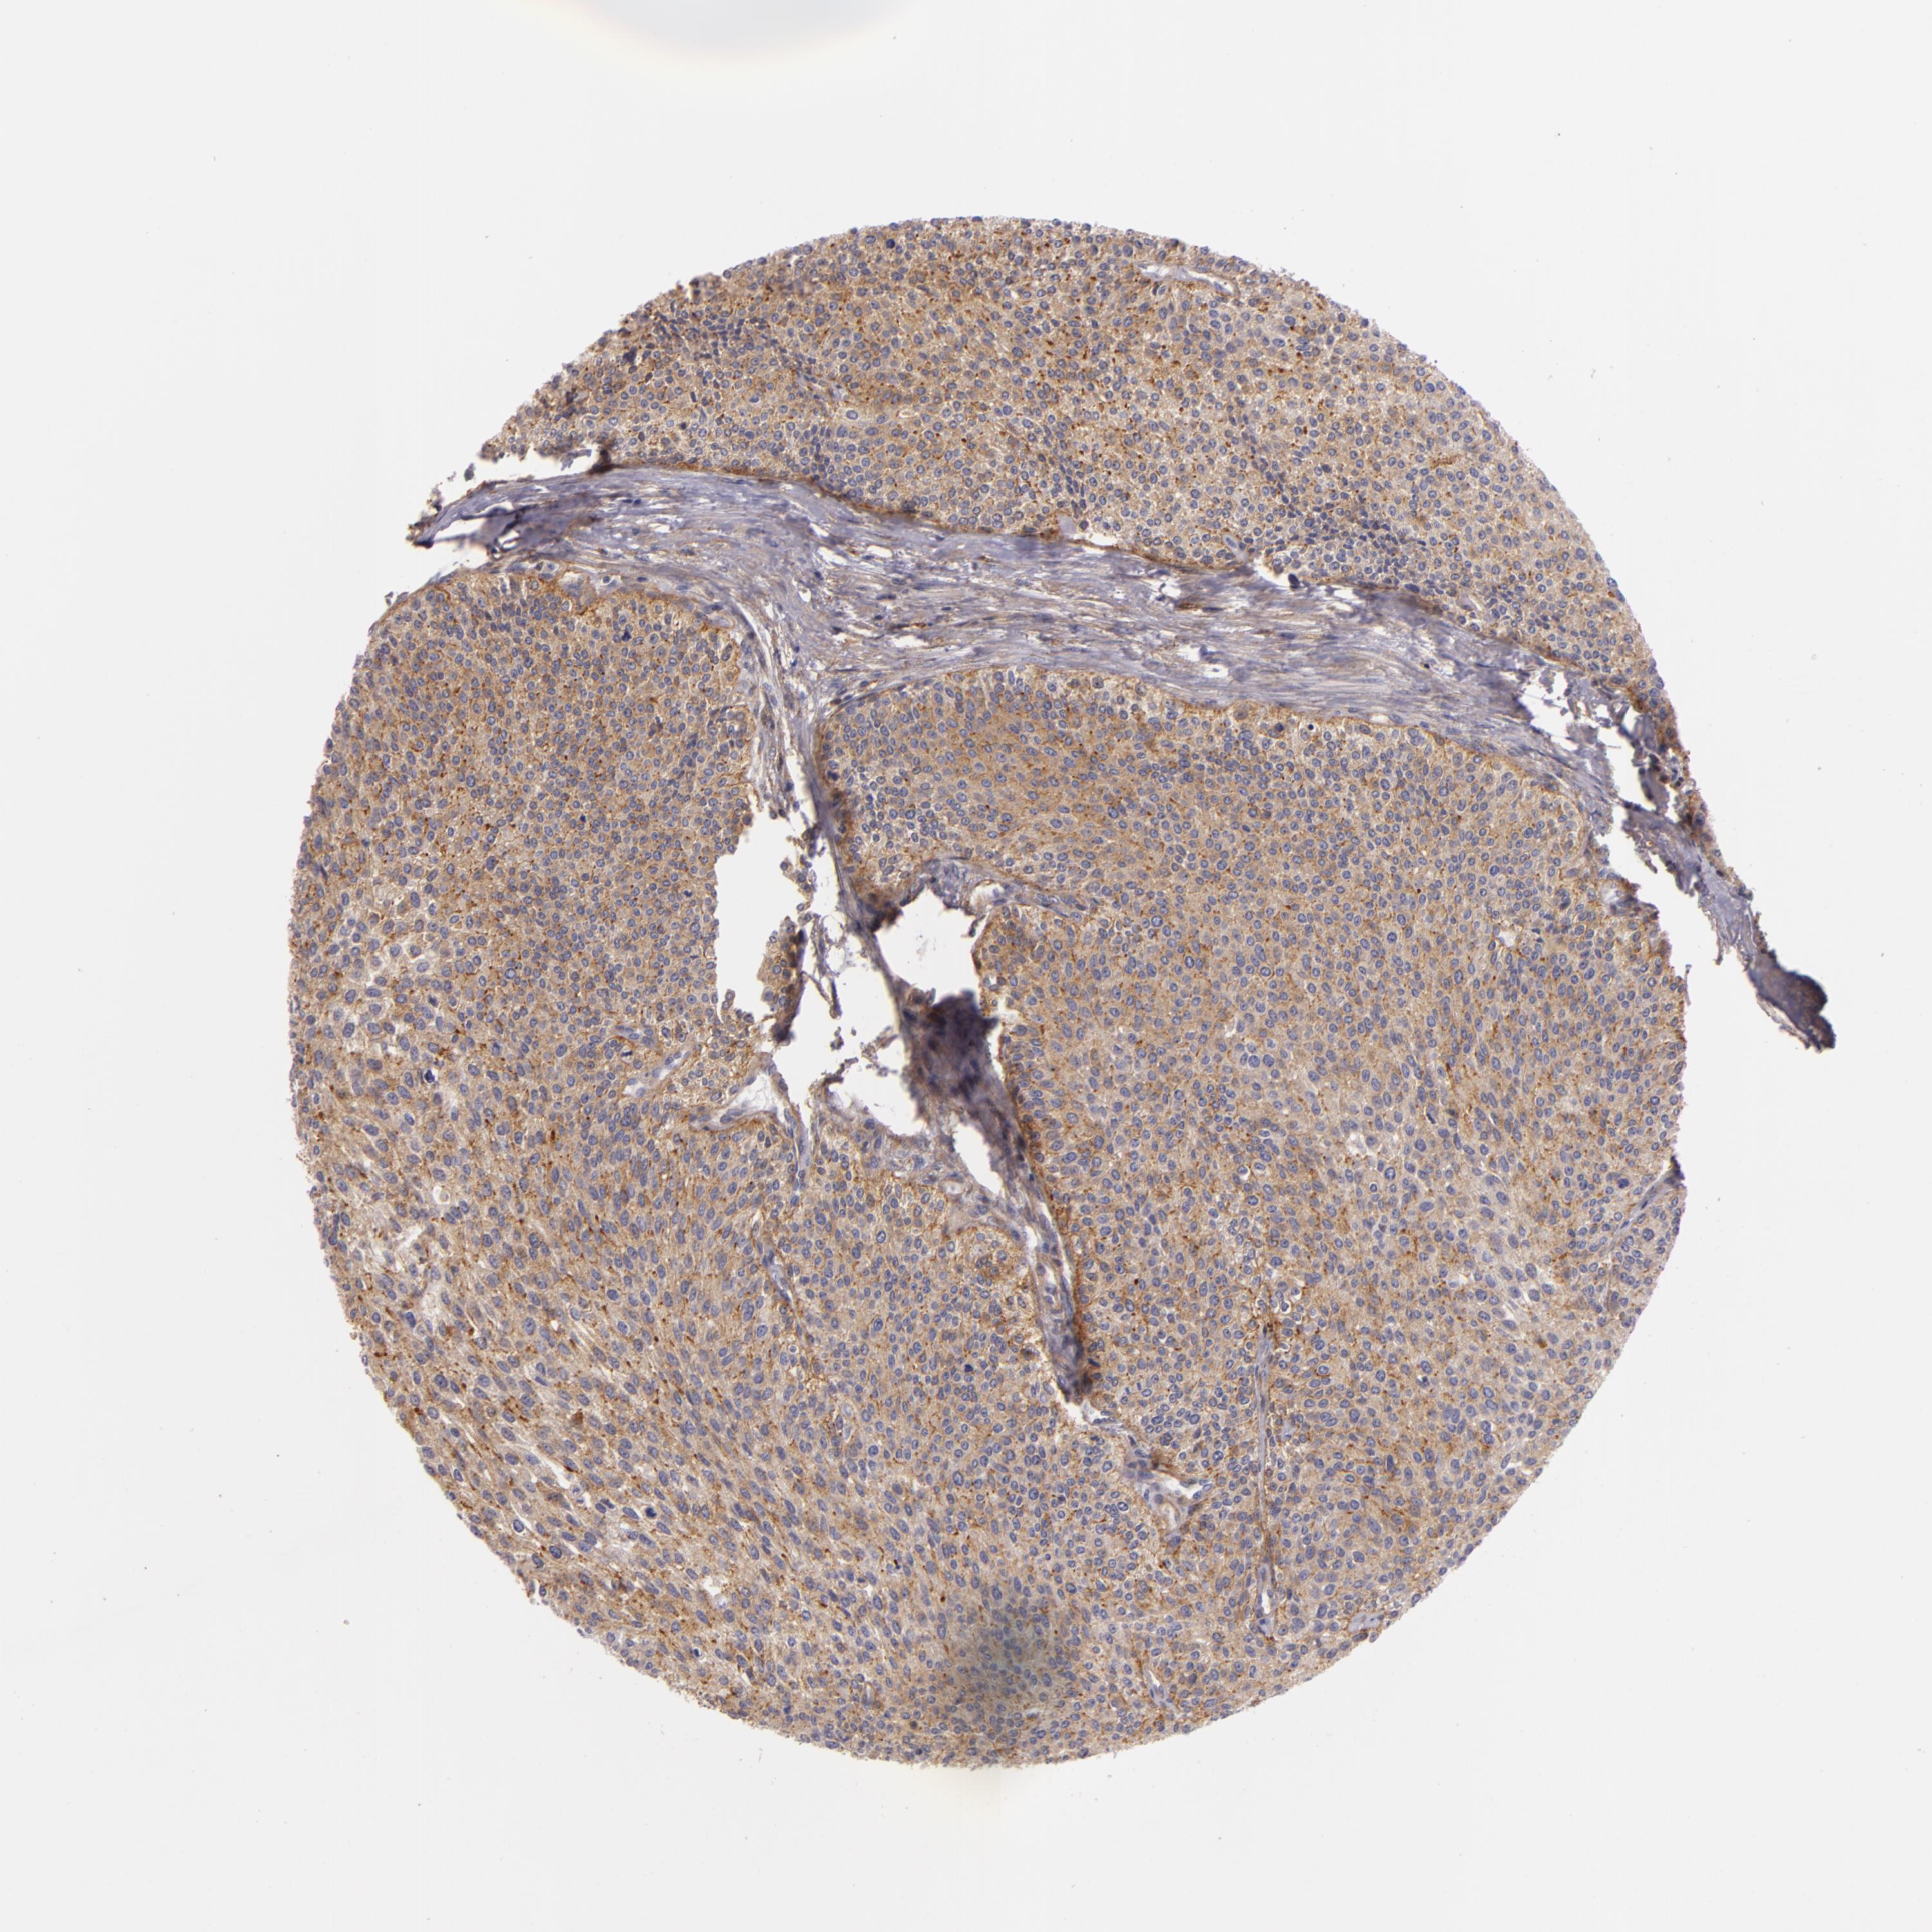

UROTHELIAL CANCER - Protein expressioni

A mouse-over function shows sample information and annotation data. Click on an image to view it in a full screen mode. Samples can be filtered based on level of antibody staining by selecting one or several of the following categories: high, medium, low and not detected. The assay and annotation is described here.

Note that samples used for immunohistochemistry by the Human Protein Atlas do not correspond to samples in the TCGA dataset.

Antibody stainingi

Antibody staining in the annotated cell types in the current human tissue is reported as not detected, low, medium, or high, based on conventional immunohistochemistry profiling in selected tissues. This score is based on the combination of the staining intensity and fraction of stained cells.

Each image is clickable and will lead to virtual microscopy that enables deeper exploration of all samples and also displays staining intensity scores, fraction scores and subcellular localization as well as patient and tissue information for each sample.

Antibody HPA001749

Adenocarcinoma, NOS